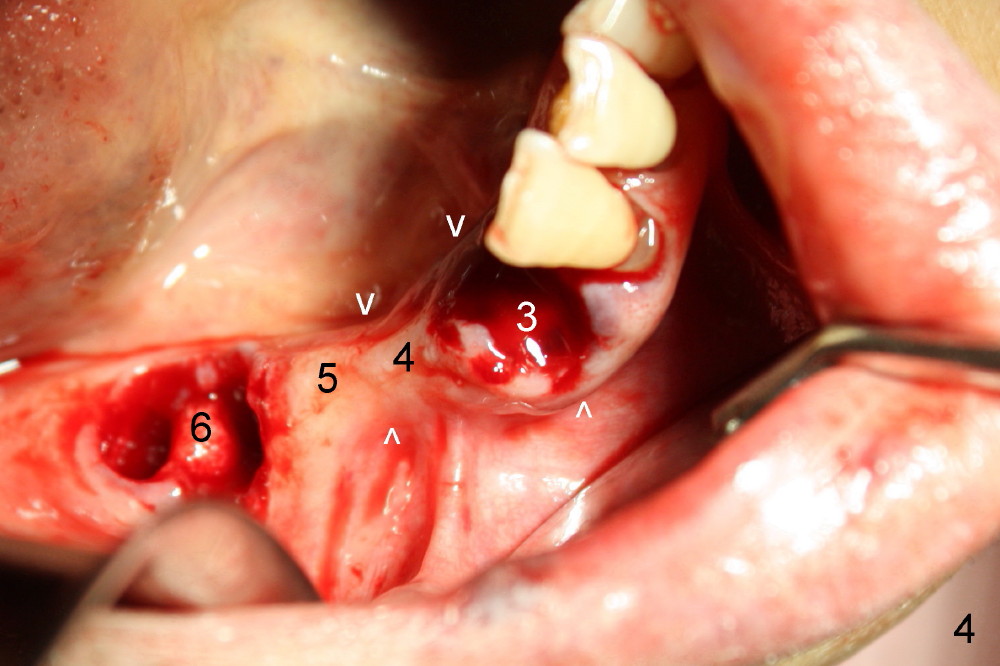

Several months ago, Philip (77 years old) was receiving chemotherapy for bladder cancer.  His lower right bridge broke down (Fig.1,2: #3-6: from canine to first molar).  The two abutment teeth (#3, 6) are nonsalvageable (Fig.4).  Ideally, immediate implant should be placed and implant-supported bridge is to be made.  The ridge at the site of #4 and 5 (premolars) is narrow.

Four months later, he returns and asks for implant restoration.  The ridge at the site of #3 is quite narrow (Fig.5).  While the socket of #3 is radiolucent (Fig.3 * under #3), there is an periapical abscess of the neighboring tooth (separate *).  It appears unsafe to place an implant at the site of #3, although anesthetic has been injected (Fig.5 *).  Instead an implant is placed at the site of #6 (5x14), further away from the infection.